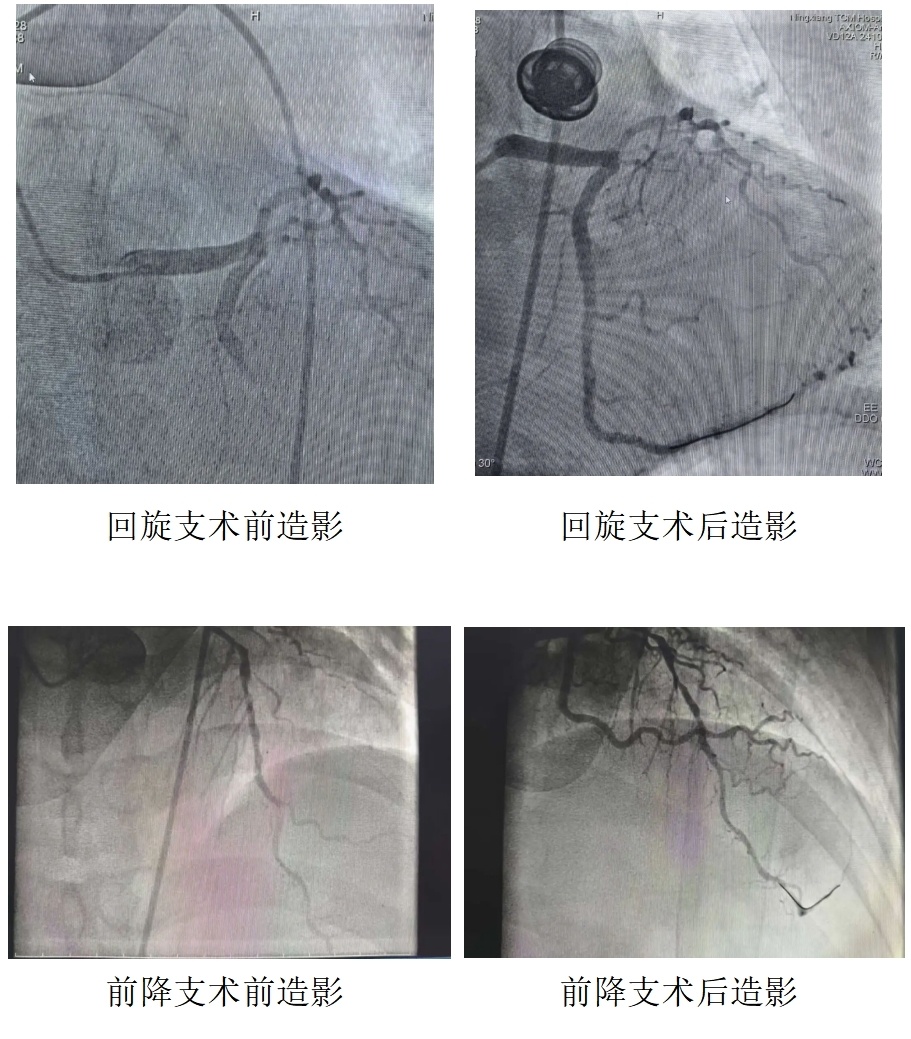

通过绿色通道,郭先生被推入导管室,医生争分夺秒开通血管、植入支架、启用心脏辅助泵,为心脏 “保驾护航”。

术后ICU团队24小时昼夜守护,严密监测生命体征,心病科团队全程介入,发挥中医特色优势,予以辨证调理、中医康复等治疗,中西医协同改善心肌供血,缓解胸闷不适,促进心肺功能恢复。